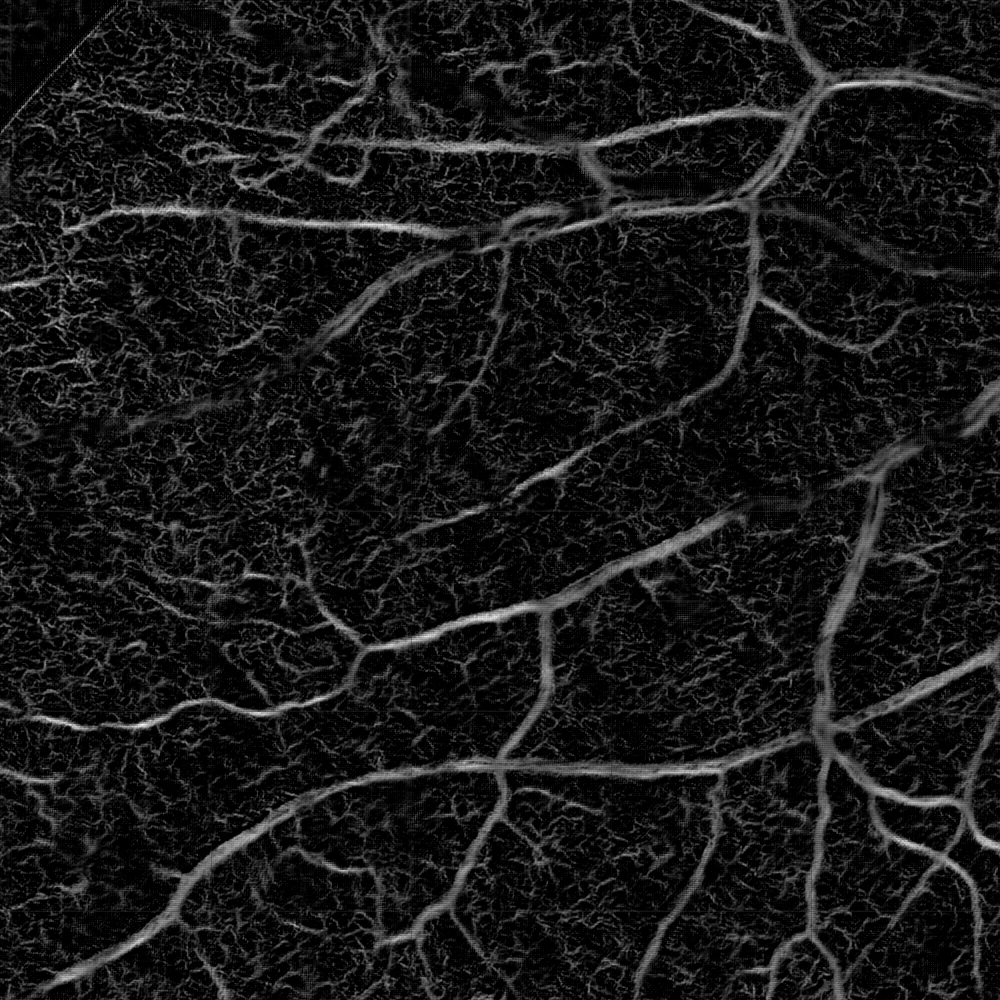

Medical images suffer from the distribution shift caused by the discrepancy in imaging acquisition protocols. Images can appear in different contrast, resolution and range of intensity values, even within the same modality. A set of examples is shown in Fig. 1. This obstacle severely impedes the learning-based algorithms reaching clinical adoption. Therefore, much effort has been spent on solving the domain generalization (DG) problem so that the deep models can robustly work on out-of-distribution (OOD) data. There are three major types of solutions: data augmentation [23, 18], meta-learning [6, 14] and domain alignment [24]. The first two strategies aim to improve the model’s generalizability by either augmenting the source domain with additional data or replicating the exposure to OOD data during training. In contrast, the domain alignment strives to align the distribution of the target domains in either image [8] or feature space [1, 15].

Fig. 4 shows a qualitative ablation study: it illustrates that the intensity representation may miss large vessels in the very high-resolution HRF images, while remains robust. In contrast, provides sharper delineation for very thin vessels in ROSE. The fusion of both pathways outperforms either pathway for most scenarios. These observations are further supported by the quantitative ablation study in Fig.6. We note that and can be used as synthetic angiograms that provide both enhanced vessel visualization and model interpretability.